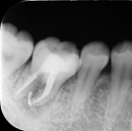

これは根尖性歯周炎(こんせんせいししゅうえん)と呼ばれる状態で、歯の神経(歯髄)が細菌感染し、炎症が根の先端にまで及んでいることを意味します。

CTで根管形態を三次元的に把握し、他の診査と併せて保存可能性を診断します。

根管の数・弯曲・破折の有無を立体的に確認。

CT画像は3次元的に歯の中の構造を可視化することで、術中も安全に治療をしたり、見逃している根管を明示するのに役立ちます。

炎症を起こした神経を除去し、根管内を無菌化した上で根充およびクラウン補綴を行いました。